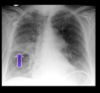

What abnormality is seen here?

left tension pneumothorax > increases left thoracic volume > shifting the heart to the right

What ees thees?

Tension pneumothorax causing tracheal shift